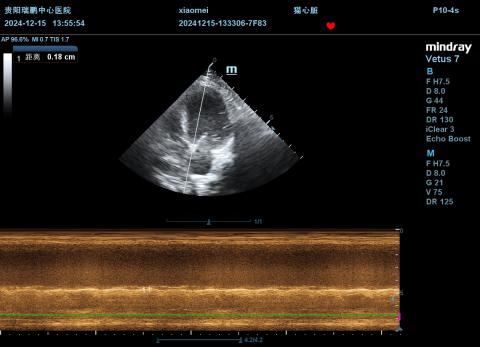

4.4.2 超声心动图(12.21)

图35-45

结果提示:

①舒张末期LVIDd:2.54-2.97cm,EPSS=0.94,左心室较12月15日扩张(LVIDd:2.54-2.97cm,EPSS=0.81);

②舒张末期IVSd=0.38-0.45cm、LVPWd=0.36-0.38cm,室间隔与左室游离壁较上次变薄(IVSd=0.50-0.55cm、LVPWd=0.39-0.55cm);

③FS=8.85-11.36%,左心室收缩功能较上次下降(FS=8.99-15.29%);

④二尖瓣瓣环扩大,轻度反流,反流速度约265.32cm/s,压差约28.16mmHg,反流流速较上次下降(MR Vmax=265.32cm/s),提示左心室收缩功能进一步下降;

⑤LA/AO=1.99,提示左心房扩张;

⑥少量胸腔积液(厚度约0.47cm),较上次明显减少;

⑦综上述,胸腹水减少,考虑与右心衰竭被控制有关,但心脏收缩功能严重受损,因此DCM各项指标均进一步变差。